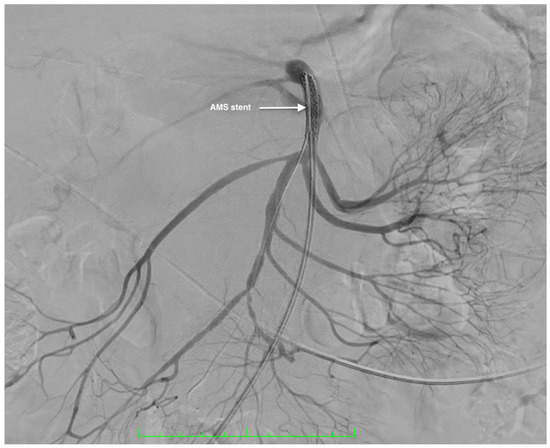

Management of a Rare Case of Superior Mesenteric Artery Aneurysm Associated with a Pancreatic Cyst Complicated by Acute Rupture: A Case Report and Review of Literature

2. Case Report